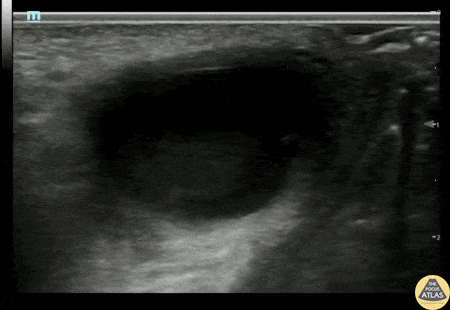

Soft Tissue - Bartholin's Gland Abscess

20s F with past medical history of multiple bartholin gland abscesses requiring drainage presented with genital pain and swelling. I&D of the abscess was attempted which was initially unsuccessful, so POCUS was performed to confirm the location of the abscess. Gynecology was then consulted for drainage and was able to successfully drain the abscess. Alexandrea Netto PA, Denver Health and Hospital Authority Katie McCabe MD, Attending Physician, Denver Health Residency in Emergency Medicine